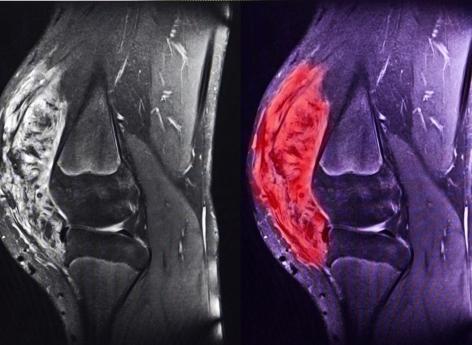

Il existe de très nombreux types de sarcomes. Ils peuvent être classés en trois grandes catégories : les sarcomes des tissus mous, les sarcomes des viscères et les sarcomes des os. Les sarcomes des tissus mous prennent leur origine dans les muscles (léiomyosarcome, rhabdomyosarcome), la graisse (liposarcome), les vaisseaux (angiosarcome), les nerfs etc... ; les sarcomes des viscères peuvent apparaître dans l’utérus ou le tube digestif (GIST) ; les sarcomes osseux se développent à partir des os (ostéosarcome, sarcome d’Ewing), et également du cartilage (chondrosarcome).